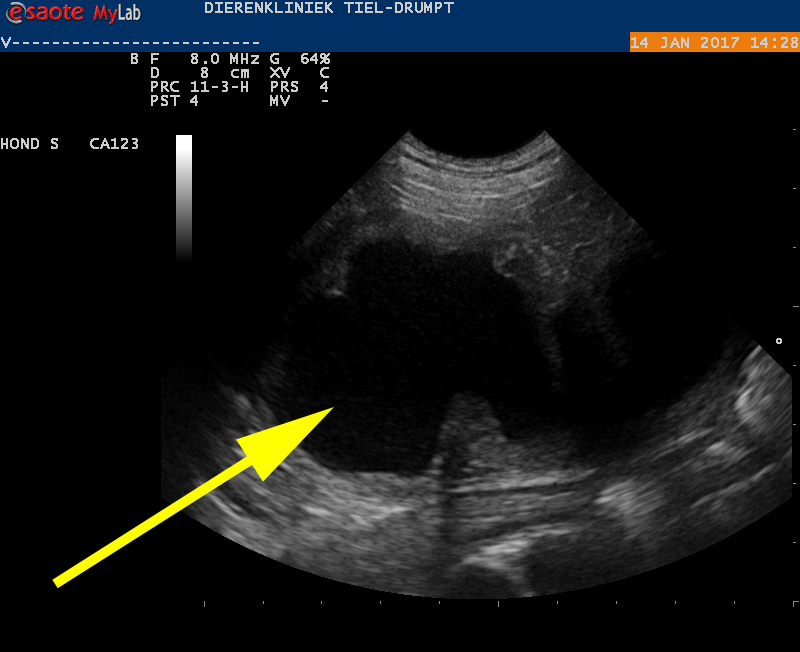

Omdat deze combinatie van vraaggesprek en onderzoek een verdenking op baarmoederontsteking naar voren bracht, werd besloten een echografisch onderzoek uit te voeren. Hieruit kwam inderdaad een baarmoederontsteking (zogenaamde pyometra) naar voren. En wat voor eentje! Dit hadden we al lange tijd niet meer zo heftig gezien, zeker niet bij de relatief jonge leeftijd van Dascha. De baarmoeder van een hond heeft een klein lichaam en 2 hoornen, die aan de eierstokken vastzitten. Bij een Cane Corso zijn de hoornen meestal iets dikker dan een potlood (of een vinger). Bij Dascha bleek uit de echo een diameter van 6 centimeter, waarbij er in het algemeen pus in de hoornen staat.